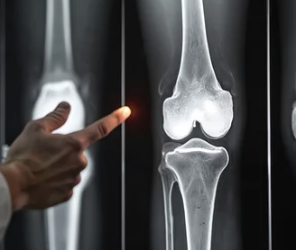

5. 무릎에 물이 차는 대표적인 원인

무릎에 물이 차는 이유는 하나가 아닙니다.

흔한 원인들

- 퇴행성 관절염

- 반월상연골판 손상

- 인대 손상

- 활액막염

- 외상 후 염증

- 통풍, 류마티스 질환